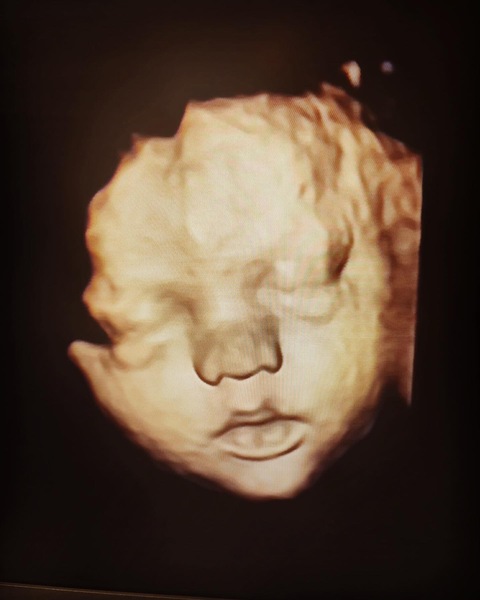

We then had our 12 week scan at the NHS and my world shattered. With a NT measurement of between 6.1 and 7mm we are in the highest possible risk category. To think I wasn't even going to have the screening at first is awful. I had taken my health for granted and seeing baby so well just 4 days before, no fluid was detected at all.

The fluid extends down babies back, which is the possible beginning of a cystic hygroma. This also puts us right up there with abnormalities.

We have seen our baby today, happily kicking and showing us their hands. That perfect silhouette and the growth progression is just right. The heartbeat strong, yet our baby is potentially very unwell.

Lots of luck with your c-section. What beautiful pictures. Poppy is a beautiful girl, and has such a wonderful mummy and daddy!